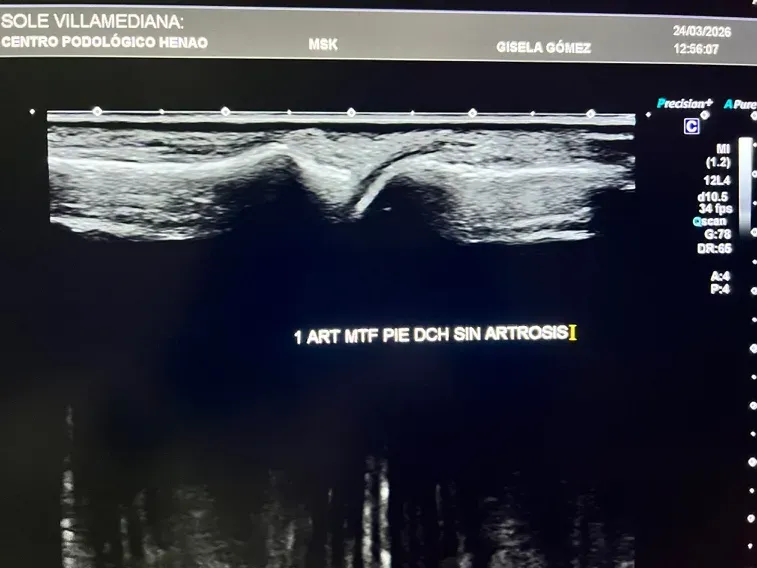

En el contexto de la artrosis del pie, la ecografía detecta:

- Cambios en el cartílago articular: antes de que la radiografía muestre nada

- Irregularidades en la superficie articular: signos tempranos de desgaste

- Inflamación articular (sinovitis): presencia de líquido o engrosamiento de la membrana sinovial

- Derrame articular: acumulación de líquido dentro de la articulación

- Osteofitos en fases iniciales: formaciones óseas que aún no son visibles en radiografía

- Estado de los tejidos blandos periarticulares: cápsula, ligamentos, tendones adyacentes

Figura 2: Ecografía de una articulación del pie sin artrosis. Se aprecia un cartílago articular conservado, con superficie regular y sin signos de inflamación.